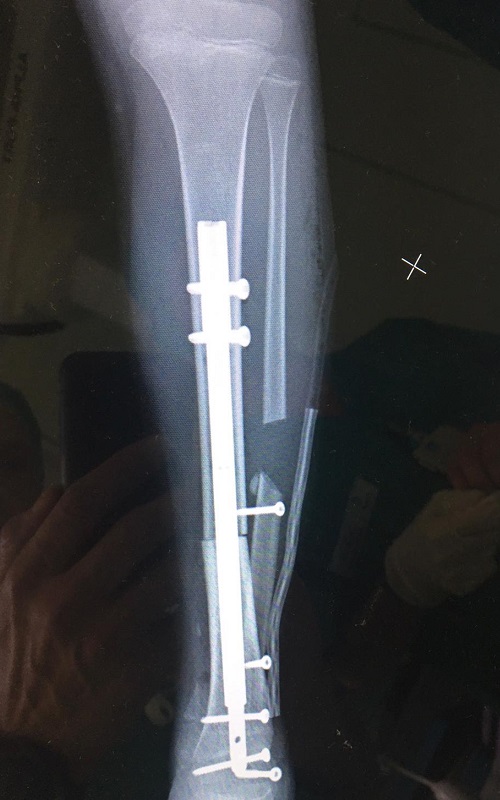

La bimba, dopo la diagnosi, è stata seguita presso il reparto di Oncoematologia pediatrica dell’ospedale Regina Margherita diretto dalla professoressa Franca Fagioli, dove ha eseguito la chemioterapia, e nei giorni scorsi è stata sottoposta all’intervento di asportazione del tumore e salvataggio della caviglia con ricostruzione con osso omoplastico da donatore e sintesi con un chiodo allungabile. La tecnica eseguita rappresenta una assoluta novità in quanto il chiodo inserito per stabilizzare l’impianto permetterà nei prossimi anni anche la regolare crescita dell’arto permettendo l’allungamento al termine della maturazione scheletrica. La chirurgia è stata pianificata nei minimi dettagli dalle due équipe di medici e ingegneri nelle settimane precedenti l’intervento. Nonostante la pandemia da COVID-19 le cure legate a questo tipo di patologie si sono svolte regolarmente e senza ritardi pur attuandosi tra enti di regioni diverse. La bimba ora sta bene ed è appena stata dimessa.

Negli ultimi 30 anni si è vissuta la straordinaria evoluzione di nuove tecniche chirurgiche specifiche per lo scheletro infantile, riducendo drasticamente il numero di amputazioni e riuscendo ad applicare nella maggior parte dei casi un approccio conservativo-ricostruttivo, volto a migliorare il recupero funzionale e ad assicurare una migliore qualità di vita ai pazienti e alle famiglie. Le strategie chirurgiche disponibili sono oggi molteplici, comprendono pianificazioni virtuali della resezione ossea e ricostruzione mediante impianti protesici espandibili, protesi costruite su misura (anche con stampanti 3D), innesti ossei omoplastici provenienti dalle Banche di Tessuto Muscoloscheletrico e trapianti di osso autoplastico vascolarizzato, mezzi di sintesi originali. Tecniche diverse sono frequentemente usate in combinazione tra loro con risultati molto soddisfacenti, ma manca ancora l’esperienza sull’evoluzione a lungo termine degli impianti utilizzati. La chirurgia dei sarcomi ossei pediatrici, con originali strategie terapeutiche e costanti innovazioni dal punto di vista della tecnica chirurgica, dei dispositivi e dei materiali utilizzati, rappresenta quindi un ambito su cui approfondire la ricerca e favorire la presenza di una rete nazionale dei centri specialistici per trovare le soluzioni ricostruttive più adatte a ogni singolo caso.